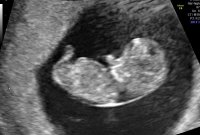

Tidlig ultralyd uke 10 (9+3). Ble satt fram til 9+5. Fosteret ble målt til 2,8 cm :Heartred

8+6 (kunne strukket det til 9+0, men hun valgte å stå på første valgte) ble satt 2-3 dager tilbake, men alt fint.